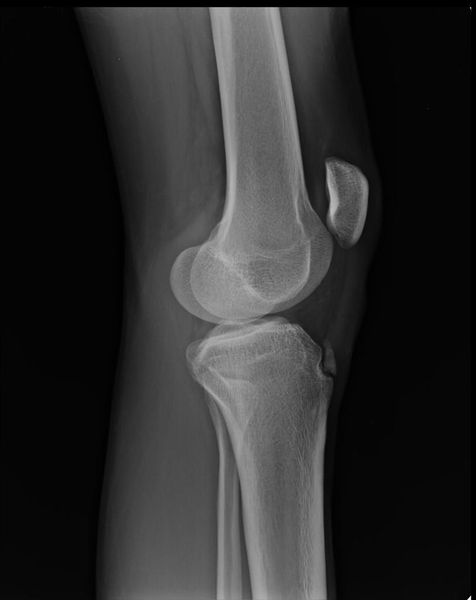

Основным методом инструментальной диагностики является рентген коленных суставов в двух проекциях, который позволяет увидеть структурные изменения бугристости [4] .

Фрагментацию с отрывом костного фрагмента лучше всего видно на боковой рентгенограмме [10] .